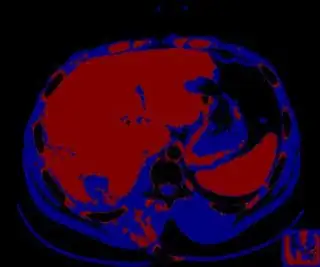

Below are some of the opened and segmented images. Of course there's more to be done in terms of

- separating out the liver region

- generalizing this to a large dataset

but hope this is at least a starting point.

You might be able to narrow down the region or interest by filtering out the darkest and the lightest regions from the segmented image. For this, use the k-means cluster centers, check for the extreme values (max and min) and remove the corresponding k values from the labeled image. Then you can look for large structures to the left of the result image. Worst case, you might get a hole on the left side when the extreme region filtering goes wrong. I've updated the code and results.